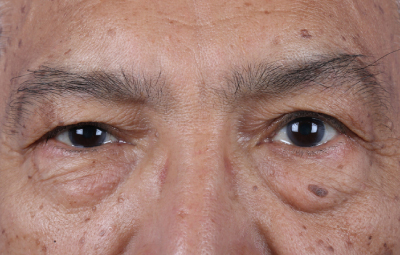

Es una ayuda diagnóstica complementaria que se utiliza para capturar imágenes de cualquier parte del cuerpo, aplicando técnicas que permitan obtener fotografías proporcionales, detalladas y nítidas; empleadas para medir, trazar, predeterminar y planear un proceso quirúrgico.

Registro fotográfico que se toma antes y después de los tratamientos odontológicos. sirve para evaluar y captar los rasgos intraorales y las características faciales.

Estas imágenes se emplean al iniciar el tratamiento mostrando el estado actual de la boca del paciente, se utilizan también para llevar un seguimiento y comparar luego del tratamiento para mostrar los resultados obtenidos.